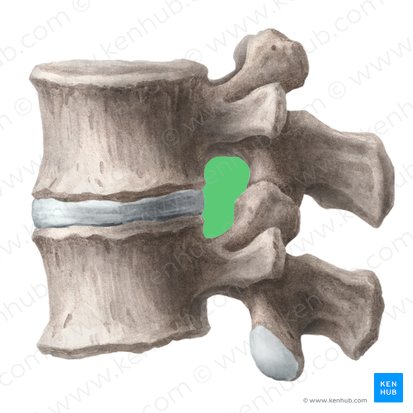

New cards

squamous suture